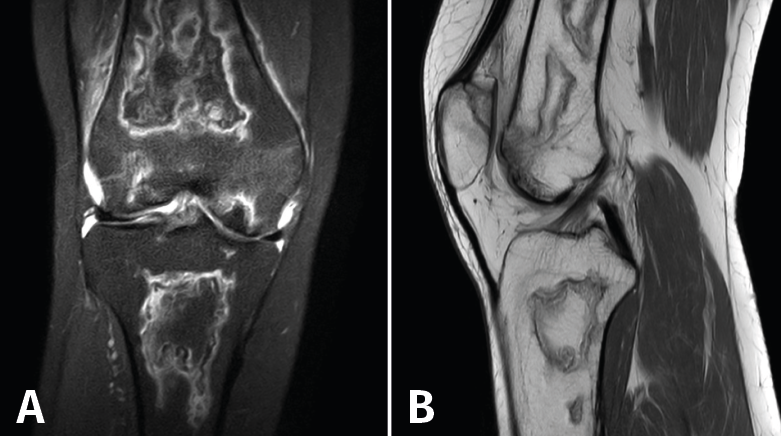

En la osteocondritis se aprecia una lesión subcondral caracterizada por resorción ósea, colapso y la formación de un secuestro.

El estudio por RM es una herramienta valiosa para diagnosticar e identificar las lesiones del cartílago. Conocer el aspecto del cartílago y saber cuánto y cuándo se lesiona, basándose en las clasificaciones actuales, permiten al radiólogo proporcionar la máxima información al clínico(20).

Figura 53. Corte de secuencia sagital (A) y axial (B) T2 Fat-Sat de RM de rodilla: lesiones osteocondrales en el fémur y la rótula.

Numerosos estudios demuestran la utilidad de la RM para definir la estabilidad o inestabilidad de la lesión en la osteocondritis, destacando su carácter no invasivo y la capacidad de valorar la progresión y la respuesta al tratamiento(21)(Figuras 53 y 54).

Figura 54. Corte de secuencia T1 y T2 Fat-Sat coronal de resonancia magnética: gran osteocondritis en el cóndilo femoral interno con edema en la medular adyacente.